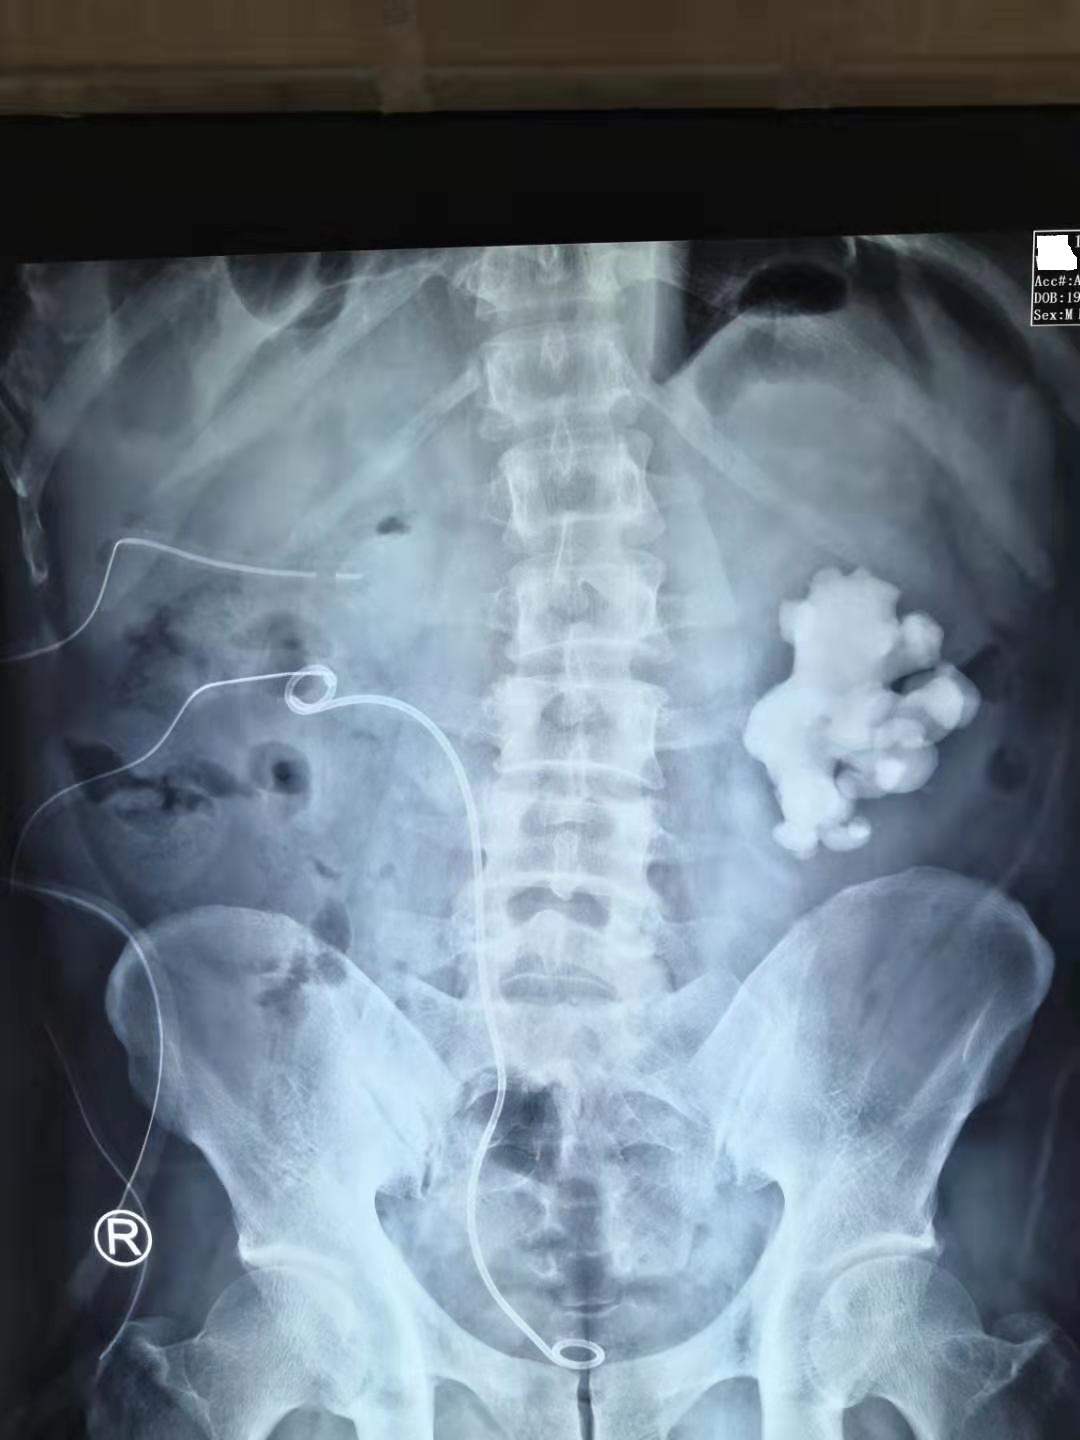

第一次手术取净右肾结石!

然后第二次手术选择分期处理左肾鹿角形结石,先把左侧肾脏约50%的结石负荷。

第二次手术取出50%左肾结石